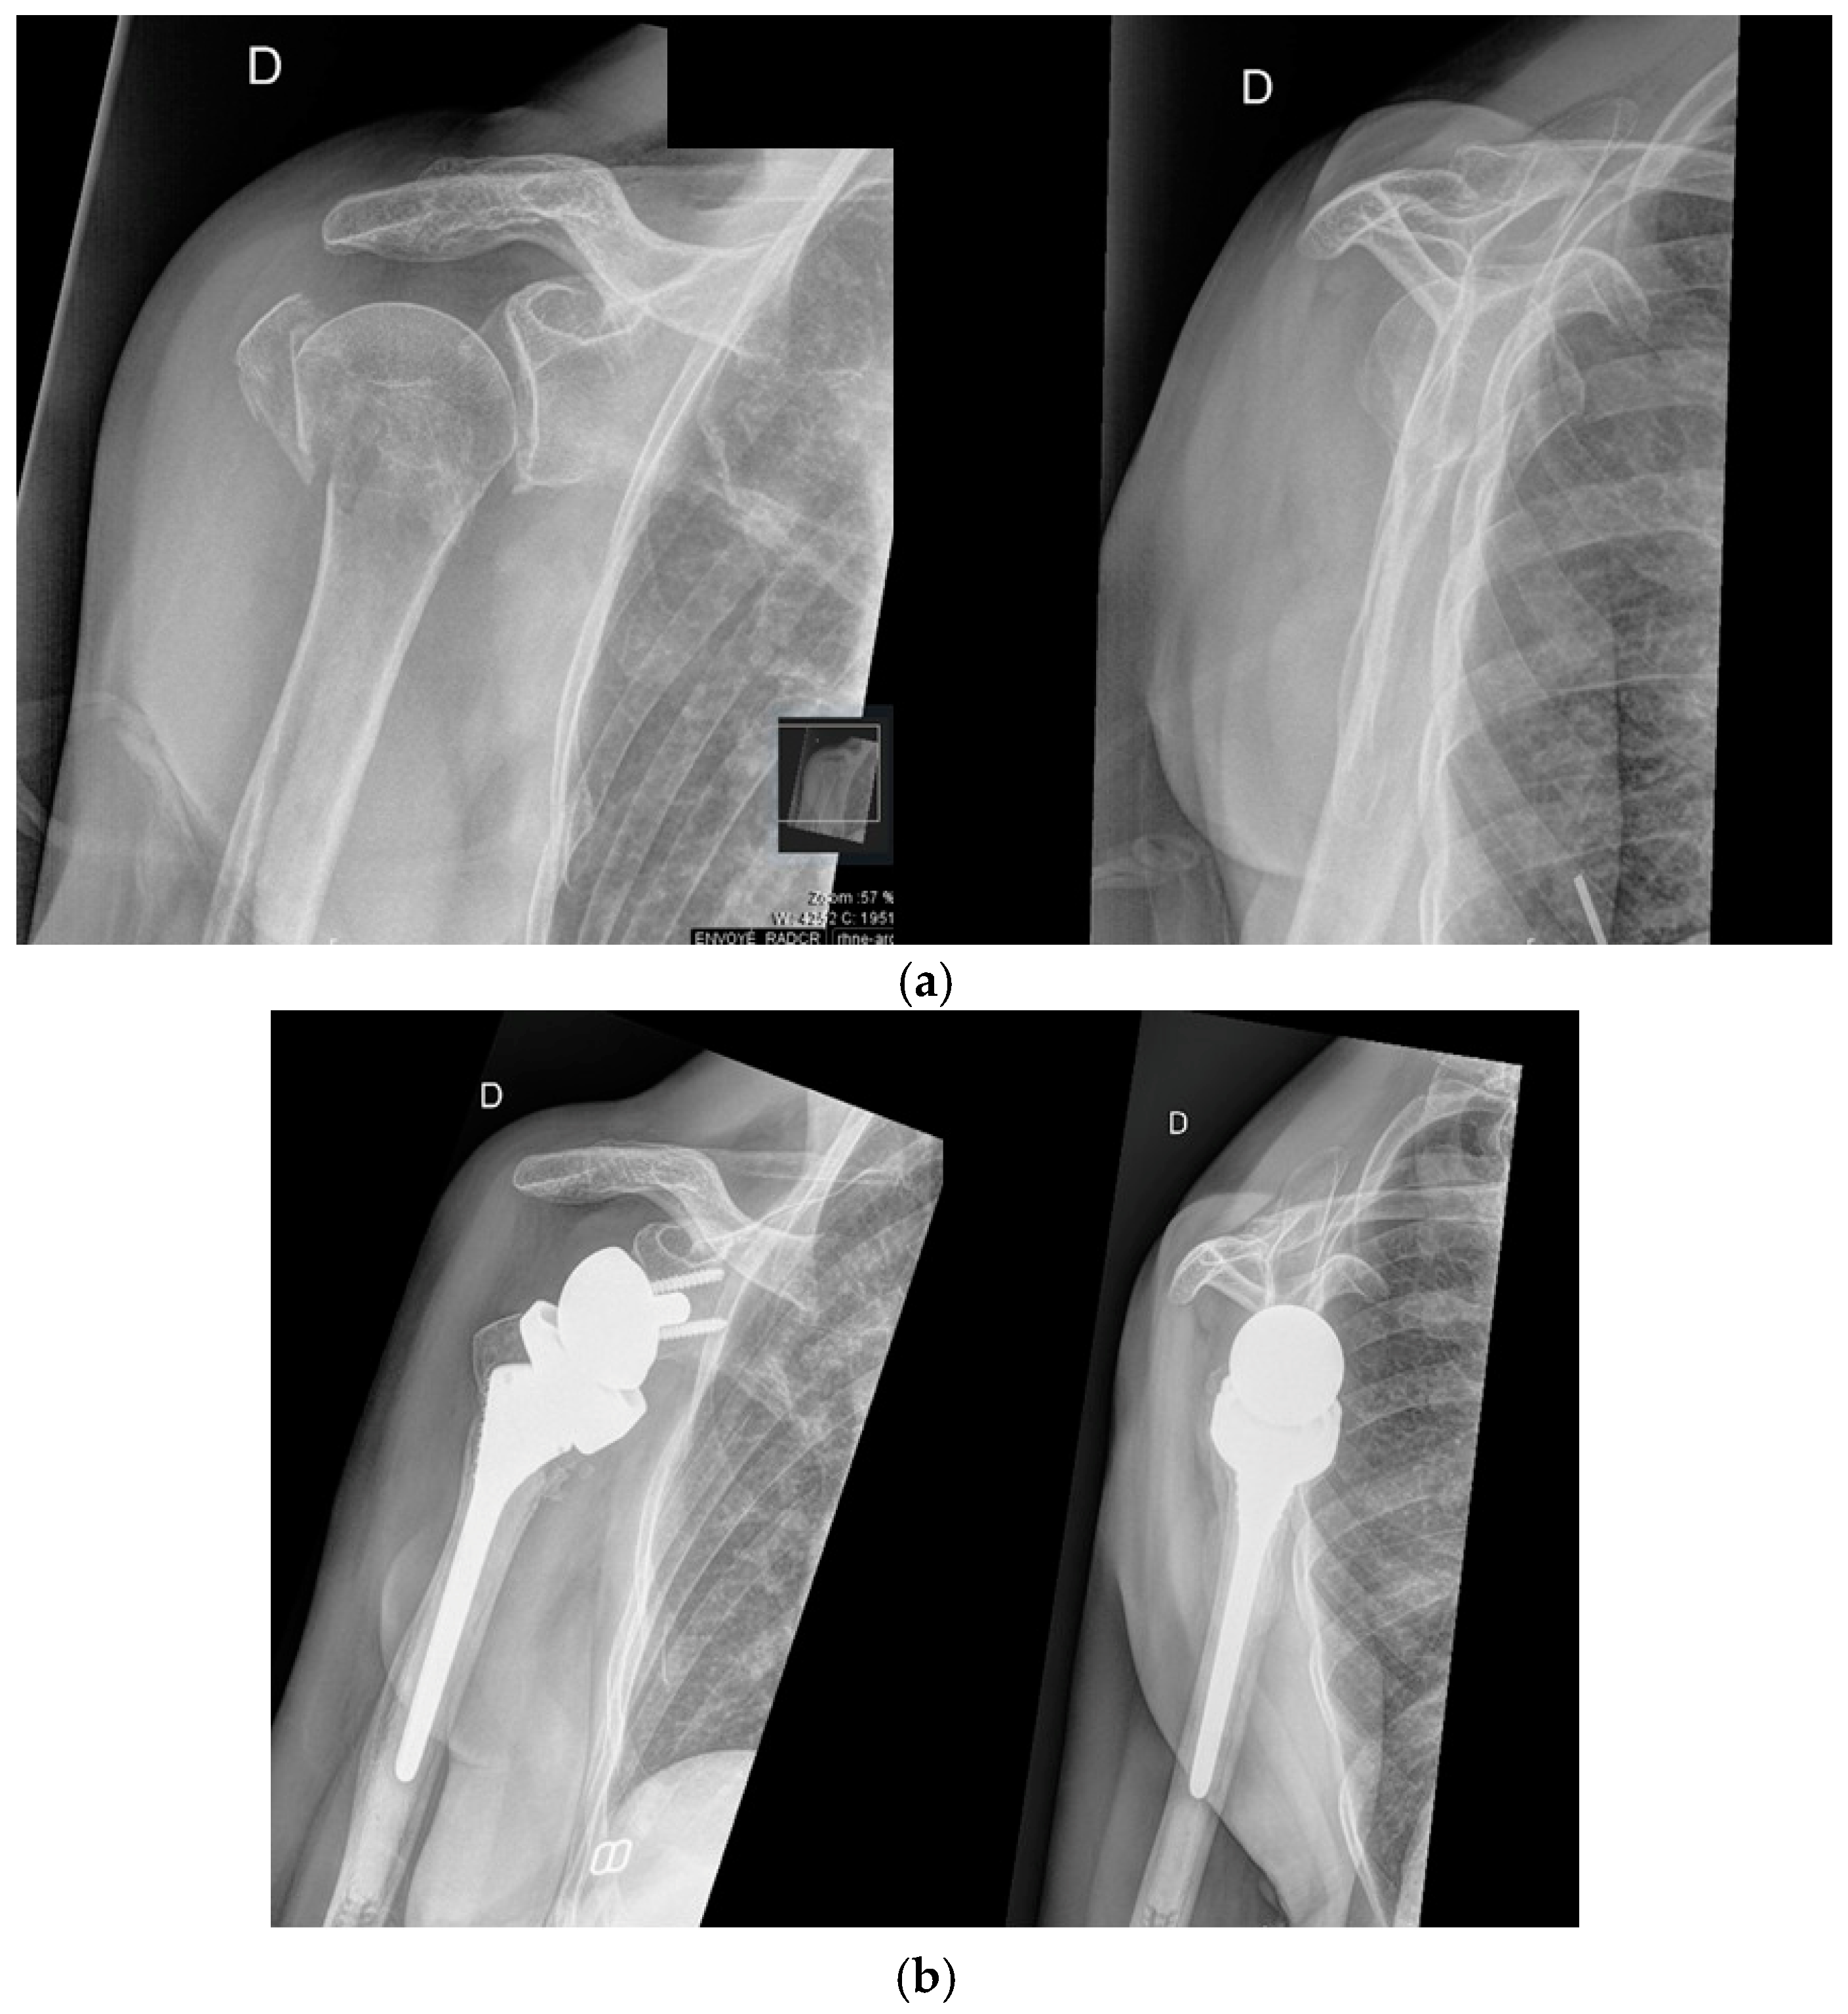

3.2. Proximal Humerus Fractures